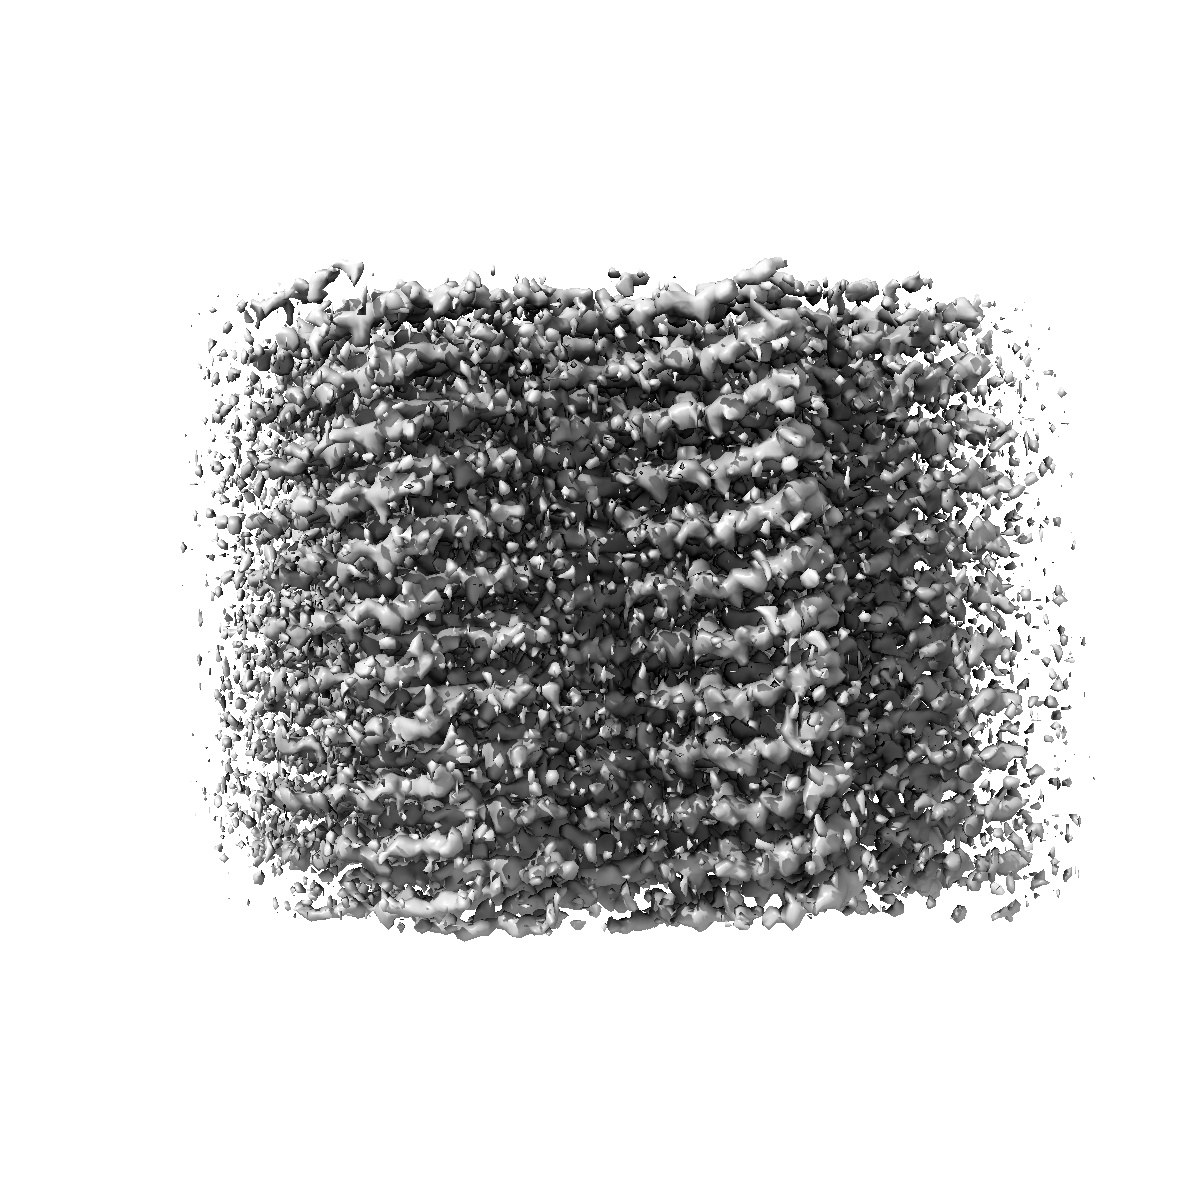

Structure of recombinant alpha-synuclein fibrils 1B capable of seeding GCIs in vivo

Helical reconstruction1.93 Å

Sample: recombinant alpha-synuclein fibril

Synthetic alpha-synuclein fibrils replicate in mice causing MSA-like pathology.

(2025) Nature , 648 , 409 - 417